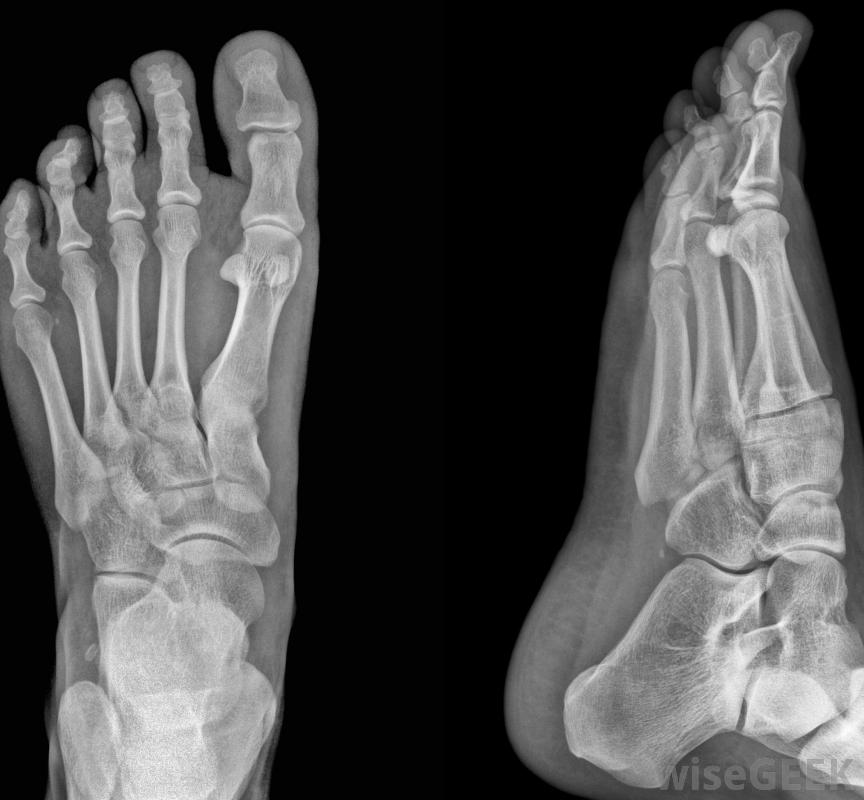

腓骨籽骨是沿着足部第一个跖趾关节的下侧发现的两个小骨头中的一个,这个关节位于大脚趾的底部。它和胫骨的籽骨一起,嵌在穿过关节的肌腱纤维中,也就是拇趾短屈肌(FHB)肌腱。这样,这些骨头支撑着FHB肌腱和拇趾长屈肌(FHL)的肌腱,在关节上起滑轮的作用,使大脚趾向下弯曲或卷曲,远离关节。胫骨和腓骨的籽骨具有双重功能,通过增加力臂来提高肌腱移动关节的有效性,并保护肌腱免受损伤在步态运动中,由于脚离开地面而产生的力。

当脚离开地面时,籽骨会影响脚的力学性能形成第一跖趾关节的是第一跖骨,足部的长骨,在大脚趾的底部和足弓之间,以及第一近端指骨,大脚趾的近端骨。这是一个髁状突或椭圆形关节,也就是说,跖骨远端或远端的凸面与指骨近端或近端的凹面相吻合,虽然脚趾在关节内可以左右移动,它的主要运动是屈伸运动:向下卷曲,向上抬起,屈伸运动是由拇短屈肌和长肌腱发起的,它们从足部和小腿相应的肌肉一直延伸到大脚趾的籽骨和指骨拇短屈肌本身分为两个部分,通过两条肌腱连接到近端指骨的底部,腓骨籽骨和胫骨籽骨都是在足底或脚底,籽骨是光滑的、圆的骨头,腓骨籽骨靠近第二足趾,FHB肌腱的每一部分都在这些小骨的周围运行,连接在近节指骨的底部。在两个籽骨之间的间隙有一个凹槽,穿过该沟槽,在附着到远端或远处之前,穿过长屈肌肌腱,指骨。另外,拇内收肌肌腱的一部分,它将大脚趾向内拉向第二个脚趾,腓骨籽骨上的嵌件。当从地面上推出时,籽骨对脚的力学性能有影响。当脚趾向下弯曲时,它们可以防止FHB和FHL肌腱被跖趾关节挤压在推开过程中,它们为FHL肌腱提供保护,它位于籽骨之间的沟壑中,而不是被跖骨和指骨压在地面上。这些骨头还充当跖趾关节的支点,增加足趾屈伸的力臂。力臂是指关节中心与通过关节的肌肉或肌腱之间的距离,也就是所谓的"力线"。换句话说,胫骨和腓骨的存在使FHB肌腱远离其穿过的骨骼当肌肉收缩时,这种增加的力矩臂提高了拇短屈肌在绕关节旋转大脚趾时的机械效率,与推离铰链最远的门的一侧而不是靠近铰链的一侧推开门更有效。